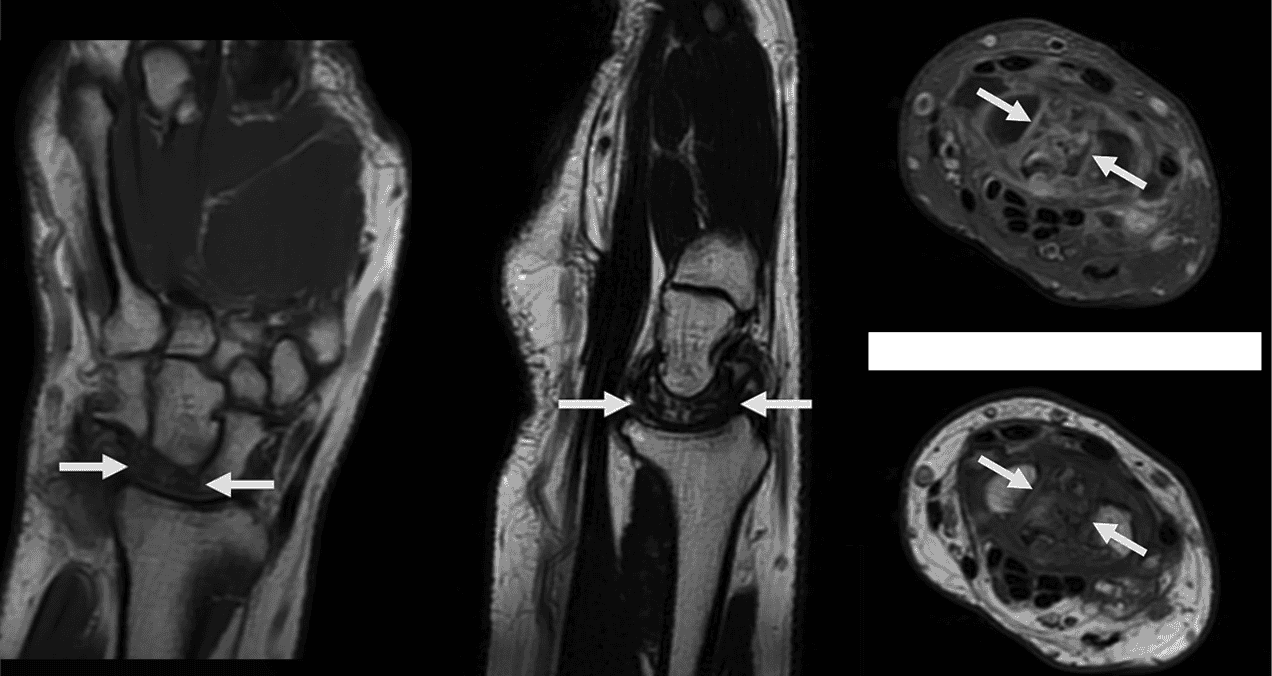

En las secuencias coronales de la resonancia, se apreció hipointensidad difusa y colapso completo del hueso semilunar. Las imágenes sagitales T2 FSE confirmaron una fractura multifragmentaria del semilunar con áreas de esclerosis asociada.

Los cortes axiales con secuencias PD FS permitieron visualizar en detalle la naturaleza multifragmentaria de la fractura y la presencia de osteoedema circundante. Con estos hallazgos, se estableció el diagnóstico de necrosis avascular del semilunar, también conocida como enfermedad de Kienböck en estadio IV según la clasificación de Lichtman, acompañada de artrofibrosis carpiana. Se decidió no realizar resonancia con contraste, ya que el estadio avanzado de la enfermedad no modificaría la actitud terapéutica.

Figura 1. La imagen de RM coronal ponderada en T1 muestra una marcada hipointensidad difusa del hueso semilunar y colapso.

Figura 2. La imagen sagital T2 FSE muestra colapso y fractura multifragmentaria del semilunar asociada a esclerosis. Los hallazgos sugieren cronicidad.

Figura 3. a. La imagen axial PD FS muestra un semilunar multifragmentario asociado con osteoedema. b. La imagen axial T1 muestra un semilunar difuso, hipointensa y multifragmentario debido a cronicidad difusa. Fotos: Caso clínico - Ricardo A Caravantes, Daniela Saenz y Favio Reyna.